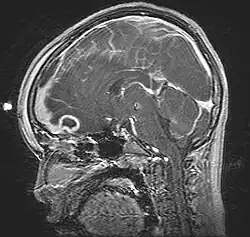

| Pott's puffy tumor, spreading towards person's brain. MRI, T1, sagittal, gadolinium contrast. | |

Pott's puffy tumor, first described by Sir Percivall Pott in 1760, is a rare clinical entity characterized by subperiosteal abscess associated with osteomyelitis. It is characterized by an osteomyelitis of the frontal bone, either direct or through haematogenic spread. This results in a swelling on the forehead, hence the name. The infection can also spread inwards, leading to an intracranial abscess. Pott's puffy tumor can be associated with cortical vein thrombosis, epidural abscess, subdural empyema, and brain abscess.

Although it can affect all ages, it is mostly found among teenagers and adolescents. It is usually seen as a complication of frontal sinusitis or trauma. Medical imaging can be of use in the diagnosis and evaluation of the underlying cause and extent of the condition. Ultrasound is able to identify frontal bone osteomyelitis,[1] while computed tomography (CT) can evaluate bony erosion, and along with magnetic resonance imaging (MRI), can better appreciate the underlying cause and extent of possible intra-cranial extension/involvement.[2][3]